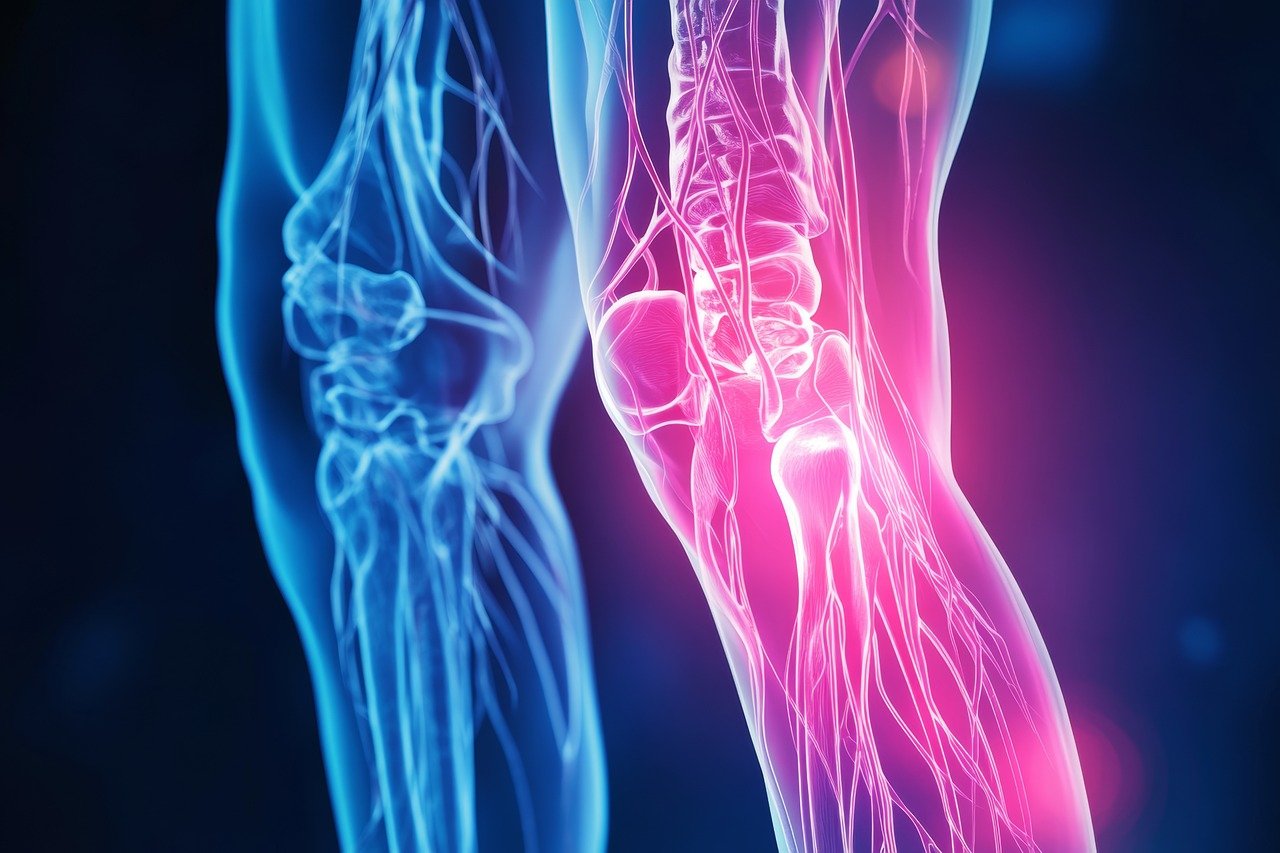

골괴사증은 뼈의 혈류가 감소하거나 차단되어 뼈 세포가 죽는 질환으로, 주로 고관절, 무릎, 어깨 등 체중이 실리는 부위에서 발생하며 초기에는 미미한 통증으로 시작되지만, 방치할 경우 심각한 통증과 기능 저하를 초래할 수 있습니다.

골괴사는 뼈에 혈액 공급이 되지 않아 뼈조직이 죽어 가는 질환입니다.

신체의 어디서든 발생할 수 있지만, 주로 대퇴부 위쪽과 팔 위쪽, 어깨, 무릎, 척추 등에서 일어나며 모든 연령층에서 발병할 수 있습니다.